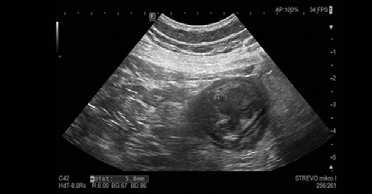

Obr. . Sonografický obraz st eva v oblasti p í ného traníku se zesílením st evní st ny na , mm.

Fig. . Sonographic image of the intestine in the area of the transverse colon with thickening of the intestinal wall to mm.